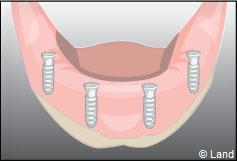

Les implants peuvent aussi servir à stabiliser un appareil amovible au maxillaire supérieur comme au maxillaire inférieur. Dans ce cas, les implants retiennent la prothèse amovible par des systèmes d’attachement.

Deux techniques sont possibles. Elles font appel à la barre de rétention ou aux boutons-pressions.